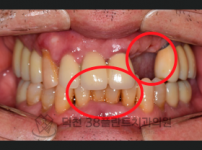

치료전후